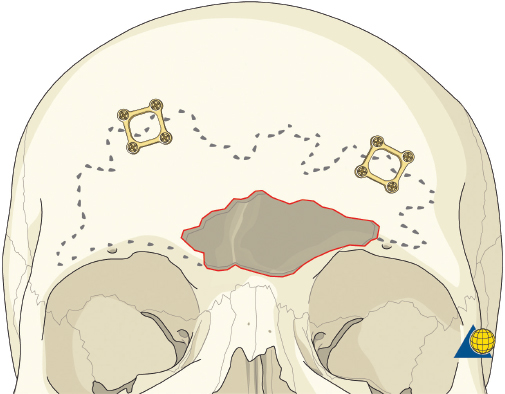

Type II fractures require more extensive surgical exposure, and generally need two- or three-point fixation. A subperiosteal dissection is used to locate, but not avulse, the medial canthal tendon. If the comminution is mild and the central fragment can be plated, the injury is treated as a type I fracture. If the central fragment is too small to be plated, transnasal wires should be used. Transnasal wires are generally easiest to place prior to any osteosynthesis of the surrounding fractures. Initially holes are drilled in the central fragment above and below the medial canthal tendon ( Fig. 63.62 ). Both ends of a 28-gauge wire (or a wire suture) are passed from lateral to medial, leaving the free ends on the medial surface of the central fragment ( Fig. 63.63 ). Once the central fragment is controlled with the wire, a drill may be used to define a transnasal path for passage of the wire ( Fig. 63.64 ). The drill must be passed posterior and superior to the lacrimal fossa, and below the frontoethmoid suture line (to avoid intracranial injury). A 14-gauge spinal needle (or angiocatheter with outer sheath removed) is then passed through the drill hole. The needle is passed in a retrograde fashion, through the ethmoid complex, from the uninjured to the injured side. A malleable retractor is placed medial to the globe on the injured side to provide protection as the spinal needle is passed. The wires are then passed transnasally through the lumen of the needle, and the needle is removed ( Fig. 63.65 ). The wire is then tightened while the central fragment is medialized with external pressure, securing the wire on a miniscrew in the frontal bone ( Fig. 63.66 ). It is critical that tension is maintained on the wire throughout fixation. Any laxity in the wire may allow the medial canthal tendon to lateralize with concomitant loss of fracture reduction. It is difficult, if not impossible, to overcorrect the reduction. Appropriate wire placement posterior and superior to the lacrimal fossa will pull the canthus medially without rotation. Transnasal wires placed anterior to the lacrimal fossa will result in lateral rotation of the central fragment and iatrogenic telecanthus ( Fig. 63.67 ).25